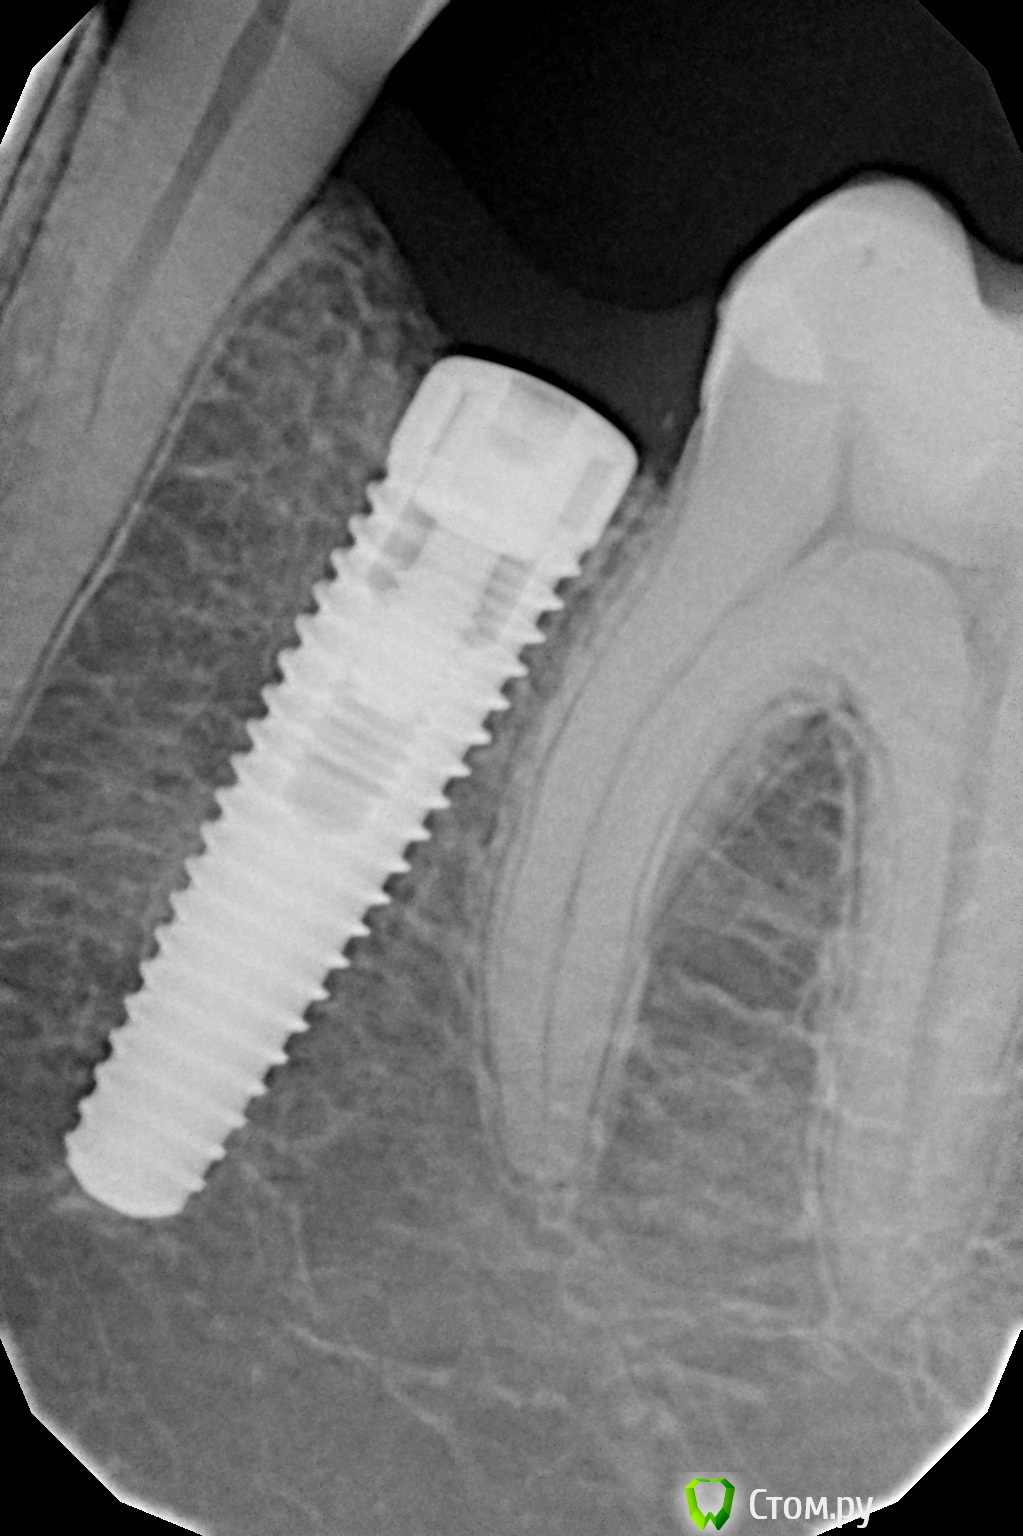

Rusty Опубликовано 23 сентября, 2014 Поделиться Опубликовано 23 сентября, 2014 Доброго дня. Подскажите, что за винты. Первый устанавливался около 7 лет назад в Москве. На следующем снимке импланты устанавливались в начале 90-х в Москве. Ссылка на комментарий

Дмитрий Никитюк Опубликовано 23 сентября, 2014 Поделиться Опубликовано 23 сентября, 2014 Нобель и 2 Ксайва. 3 Ссылка на комментарий

Rusty Опубликовано 23 сентября, 2014 Автор Поделиться Опубликовано 23 сентября, 2014 Нобель и 2 Ксайва.Сомнения по ксайву, может анкилос? Ссылка на комментарий

Дмитрий Никитюк Опубликовано 23 сентября, 2014 Поделиться Опубликовано 23 сентября, 2014 Сомнения по ксайву, может анкилос? Я в себе не сомневаюсь))). Анкилоз настолько специфичный имплантат, что спутать его с Ксайвом очень сложно. 7 Ссылка на комментарий

SDC Опубликовано 23 сентября, 2014 Поделиться Опубликовано 23 сентября, 2014 (изменено) Нобель и 2 Ксайва.Xive 3.4 справа и 3.8 слеваИ условий для протезирования нет...и на нобеле тоже Изменено 23 сентября, 2014 пользователем SDC 1 Ссылка на комментарий